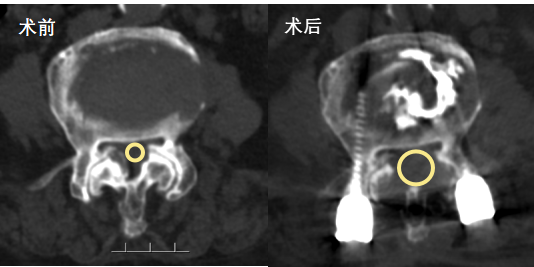

冯学烽主任表示,综合检查结果和临床症状,考虑梁婆婆是摔倒后椎管压迫脊髓加重损伤,单纯治骨盆骨折无法解决行走问题,需要做传统的腰椎的开放减压内固定手术才能从根本上解决问题。

手术由骨伤一科冯学烽主任与骨伤二科郭锋副主任联合主刀,先经2个小切口为骨盆置入3枚空心螺钉固定,再通过背部2个2.5cm小切口,完成腰椎减压、内固定及骨水泥加强操作,全程出血少、创伤小,减压效果显著。